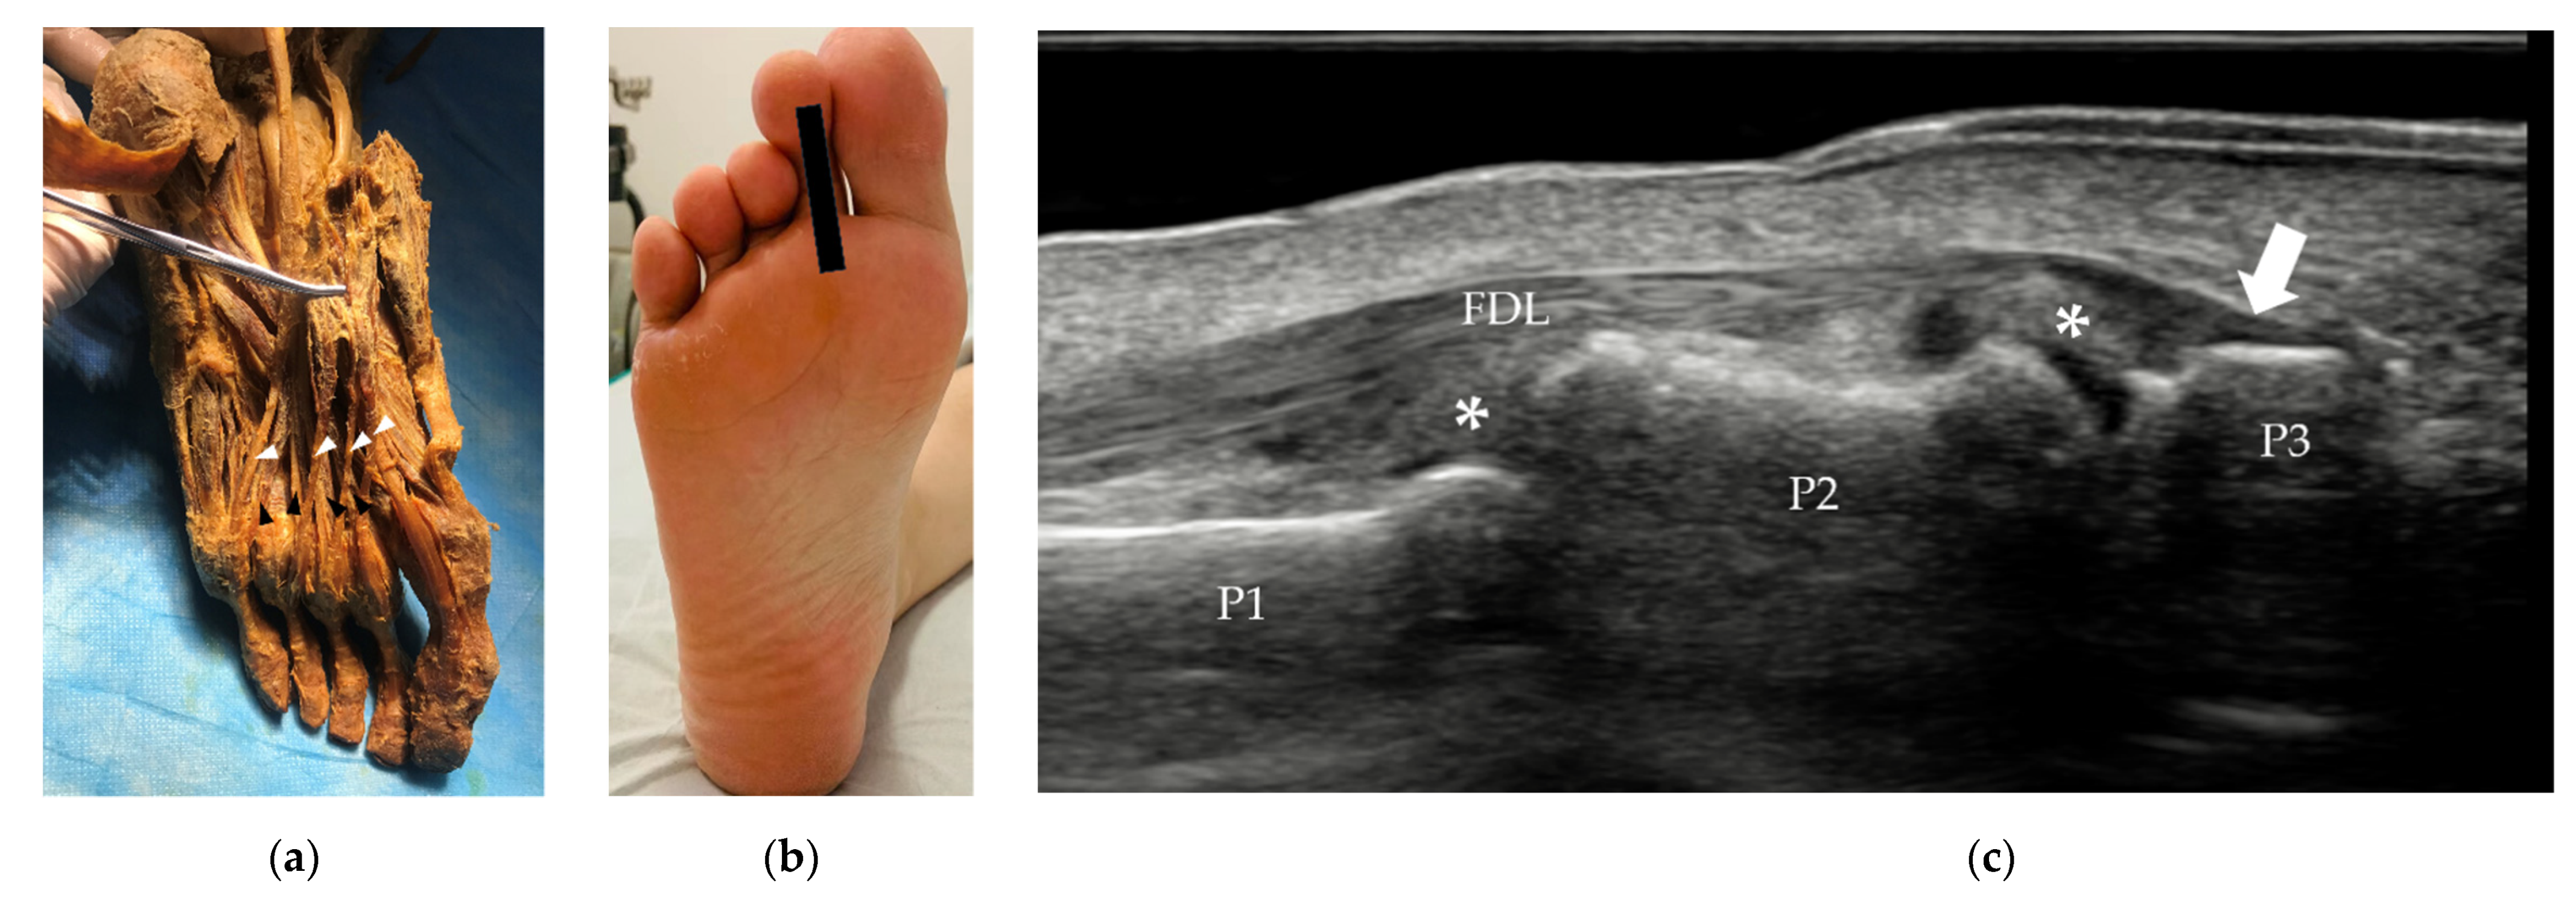

3.2.1. Tendons and Muscles of the Dorsal Foot

3.2.2. Tendons and Muscles of the Plantar Foot